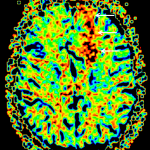

Indication: Seizure

- Peripherally-located mass in the anterior aspect of the left frontal lobe measuring 4.5 x 5.5 x 5 cm

- The mass is largely nonenhancing, though there may be minimal nodular enhancement along its anteromedial margin

- Central cystic component

- No corresponding restricted diffusion

- No substantial surrounding vasogenic edema

- Corresponding mass effect with local sulcal effacement and 1 cm left-to-right midline shift and subfalcine herniation anteriorly

- No evidence of downward transtentorial herniation or hydrocephalus

Oligodendroglioma